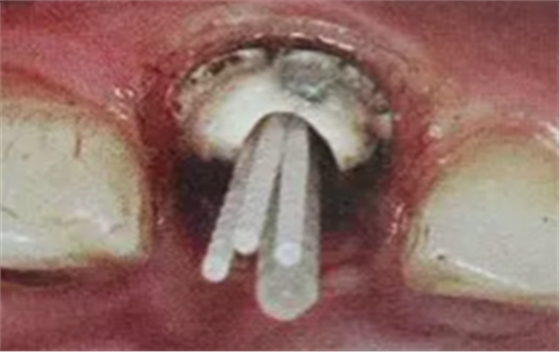

普通纖維樁對圓形截面的根管適合性較好,面對不規(guī)則時(shí)(橢圓形、喇叭形等)根管適應(yīng)性差,難以取得好粘接和修復(fù)效果。

輔樁的運(yùn)用

輔樁的運(yùn)用可改善這些適應(yīng)性的問題

(ELLIPSON 技術(shù))

(超聲預(yù)備根管完成)

ELLIPSON 技術(shù),采用超聲預(yù)備鉆對扁圓形根管進(jìn)行直接預(yù)備,改善了樁核根管的適應(yīng)性。有效的保存了根管牙體組織,從而增強(qiáng)了粘接面積,,減少樹脂水門汀的厚度,提高根管內(nèi)纖維樁的粘接強(qiáng)度。

(插入橢圓形纖維樁)